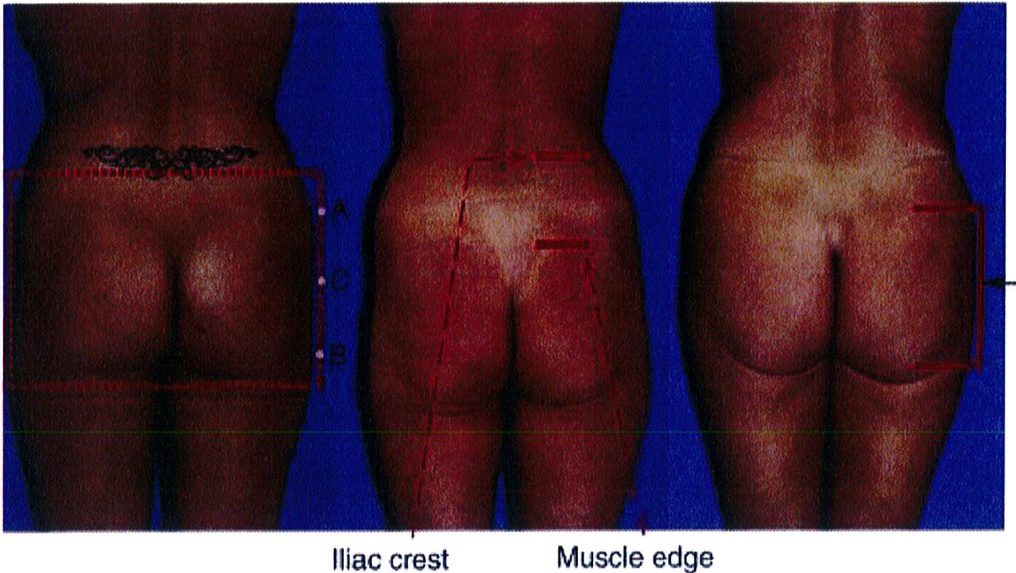

Việc phân loại các loại khung được thực hiện bằng cách so sánh và đối chiếu lượng chất béo có sẵn trong 3 vùng cụ thể. Điểm nhô ra nhất ở vùng hông, giới hạn trên được đánh dấu là điểm A, điểm nhô ra nhiều nhất ở vùng đùi ngoài

là điểm B và điểm giữa mặt ngoài mông là điểm C (Hình 4).

Sự kết nối các điểm A và B ở mỗi bên của cơ thế dẫn tới việc xác định 4 loại khung cơ bản: Hình chữ A, hình chữ V, hình vuông và hình tròn (Hình 5).

Điểm C có 2 chức năng: Đầu tiên là giúp phân biệt dạng mông tròn hay vuông. Mông tròn có lượng mỡ dư thừa ở điểm C này nhưng mông vuông thì có lượng mỡ bằng nhau hoặc lệch bên (Hình 5). Chức năng thứ hai và cũng là quan trọng nhất của điểm C là chúng giúp đánh giá mức độ lõm xuống ở điểm C trong mông vuông, mông hình chữ A hoặc hình chữ V. Mức độ lõm này được phân thành nhiều mức độ: 0, nhẹ, vừa, nặng (Hình 6).

Khung vuông là phổ biến nhất, gặp ở khoảng 40% số bệnh nhân. Vị trí A và B tương tự nhau, đặc trưng cho phần mông hình vuông để khi các điểm này nối với nhau sẽ được một hình vuông (Hình 7 và 8). Điểm C có thể có các mức độ lõm (thiếu mô mỡ) khác nhau. Đây là dạng khung dễ chỉnh hình nhất trong cả 4 kiểu khung vì bất kỳ sự thay đối nào ở 1 trong 3 điểm A,B,C đều có thể biến khung này thành dạng khung khác.

Dạng tròn gặp ở khoảng 15% số bệnh nhân. Dạng này có đặc điểm là xuất hiện lượng mỡ thừa ở điểm C. Khi cả 3 điểm (A, B và C) được kết nối với nhau, một đường cong hình chữ C sẽ được hình thành (Hình 10). Điểm C rất quan trọng vì nó giúp phân biệt khung tròn với khung vuông. Khi điểm C lõm dần, khung từ dạng tròn chuyển dạng vuông.

Khung chữ A gặp ở khoảng 30% bệnh nhân. Khi nối các điểm A và B, tạo ra hình dạng gần như chữ A (Hình 11). Hình dạng này đặc biệt vì chúng tích nhiều mỡ ở hơn ở vùng đùi ngoài phía trên (điểm B) và ít chất béo hơn ở vùng hông bên (điểm A). Lý tưởng nhất là điểm A nhô ra nhiều hơn một chút. Lúc này, khi rút chất béo ở điểm B đi, mông bắt đầu có dạng vuông. Điểm C có thể bị lõm đi nhiều, song ở dạng này hầu hết các trường hợp chỉ lõm mức nhẹ hoặc trung bình.